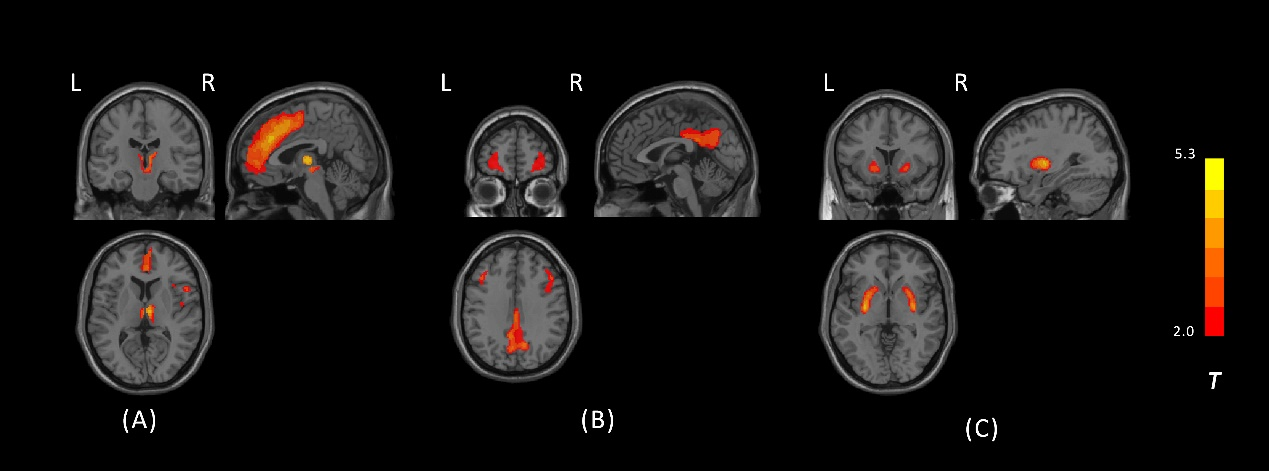

fig1

Three Components Significantly Associated with PSP